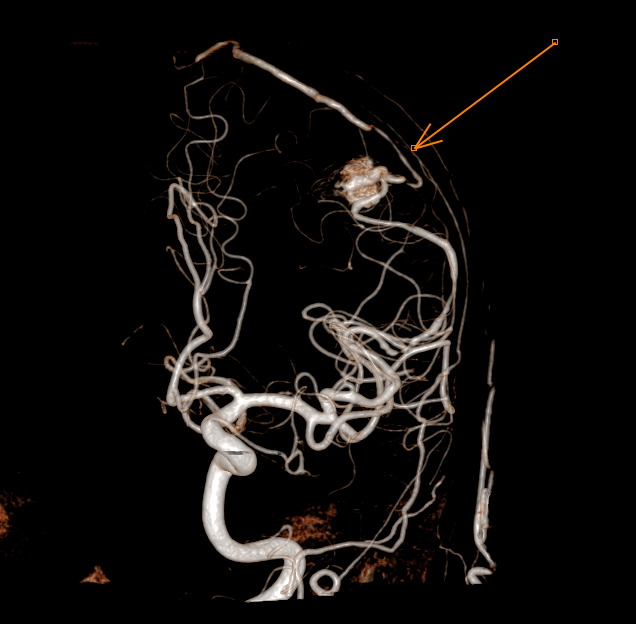

Malformations artério-veineuses (MAV)

Figure 2. Absence de reliquat après exclusion chirurgicale de la MAV